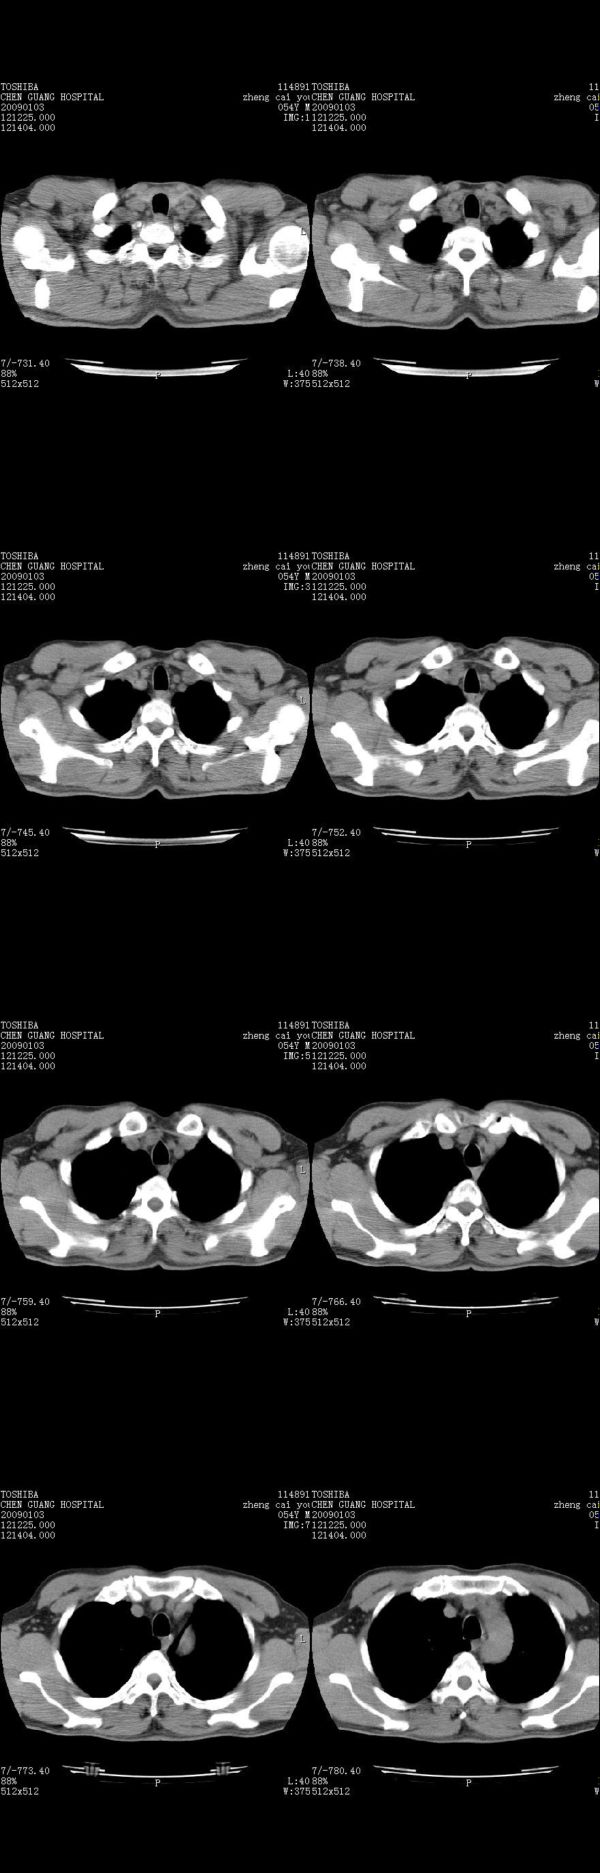

男,54岁,右侧胸部疼痛,平时吸烟,有抽烟后咳嗽咯痰史。昨天没把xiphoid软件吃懂,所以没把纵隔窗图像处理出来!请各位老师帮忙看一下右肺门有没有问题?谢谢!!!!!!!!!!

右肺上叶后段近气管旁仍可见一结节灶,不除外为肿大的淋巴结影。

气管前腔静脉后似见增大淋巴结影,肺门区未见明显肿块影。肺窗示右肺中叶外侧段透亮度增高,可过一段时间再查一下对比一下,毕竟是自己的至亲,又有条件,辐射就顾不得了。

为什么没有肺窗,我觉得右肺上叶前后段支气管间应该加扫薄层,还是小心点吧,其他到没有什么问题

也觉得还好吧,只是右下肺动脉显粗了点,纵膈有钙化淋巴结,再有肺窗就更好了

各位老师:奇静脉增宽,肺上未见明显实变,这还需注意观察些什么?????

右侧肺门影增大,不除外增大淋巴结可能

上腔静脉后淋巴结影,不知道最后结果怎么样?